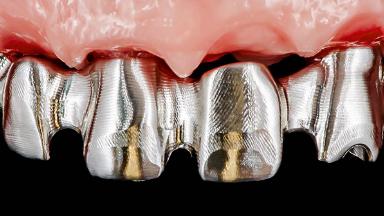

Rehabilitating an Edentulous Maxilla with a Fixed Dental Prosthesis Following Provisional Immediate Loading

This case features the flapless computer-guided placement of 7 bone-level implants, distributed to provide maximal support for the prosthetic framework. A rigid one-piece metallic framework was utilized as an interim restoration to reduce the risk of fracture associated with this prosthetic design. As part of the clinical examination, the SAC Assessment Tool was used, resulting in a surgical and restorative risk classification as “complex”.

Prosthesis Type FDP

Loading Protocol Immediate

Esthetic Risk High